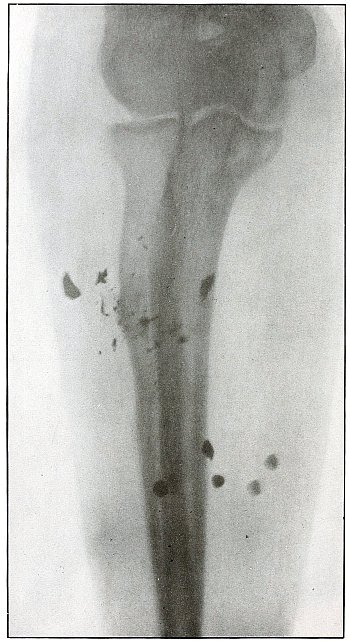

| 8. |

Gunshot fracture, humerus |

26 |

| 9. |

Gunshot fracture, humerus, lodgment of missile |

28 |

| 10. |

Gunshot fracture, humerus, lodgment of missile |

30 |

| 11. |

Gunshot fracture, humerus |

32 |

| 12. |

Gunshot fracture, humerus |

34 |

| 13. |

Gunshot fracture, humerus |

36 |

| 14. |

Gunshot fracture, humerus, lodgment of missile |

38 |